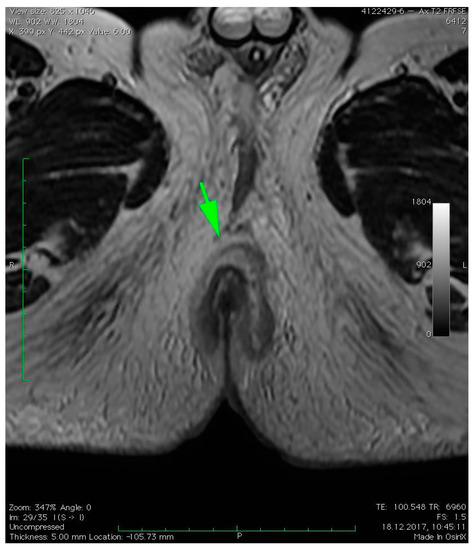

2.2. Radiologic Imaging

3. Case Presentation